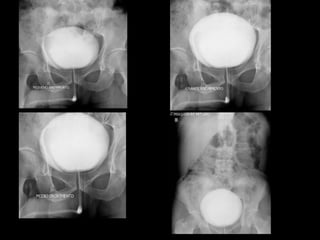

 Pesquisa de refluxo vesicoureteral - 35x43

UCG: graduação do refluxo

Vesicoureteral Reflux and Reflux Nephropathy

Willian Carlos Nahas, Anuar Ibrahim Mitre, Sami Arap, Gilberto Menezes de Góes

Fernbach et al. RadioGraphics 2000; 20:155–168.

Berrocal et al. RadioGraphics 2002; 22:1139–1164.